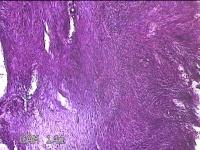

子宫肌瘤

性别

女

年龄

41岁

临床诊断

子宫肌壁间肌瘤

一般病史

发现子宫肌瘤4年余。

标本名称

大体所见

灰白色圆柱形条索状组织10.5x7x1.3㎝一堆,切面均为灰白色结节状或编织状,质硬。

图1